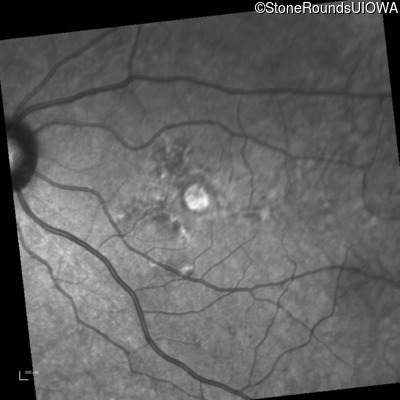

Infrared Fundus Photograph - Left - 20/50 -1

Exemplar